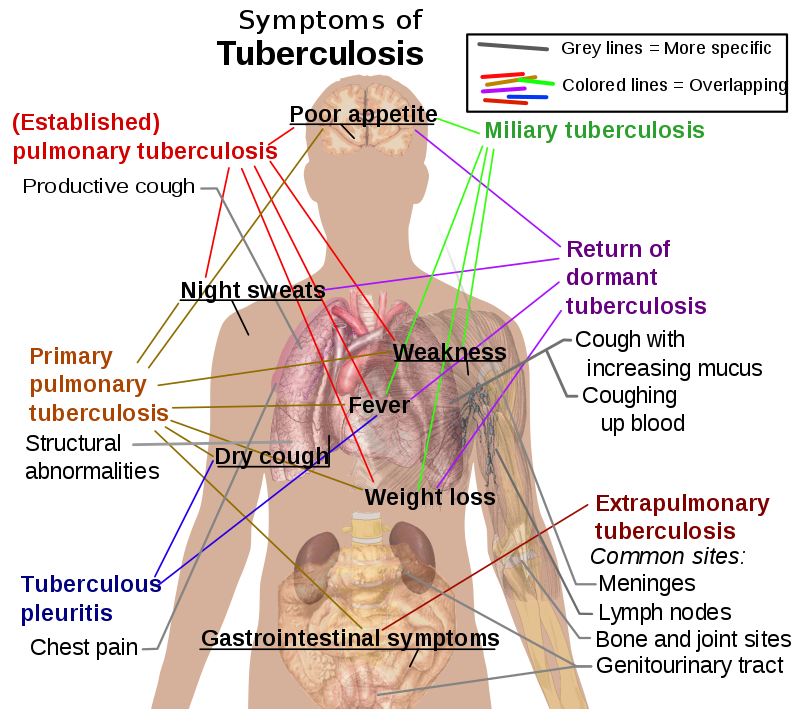

Symptoms of tuberculosis (TB) include:

- Fever

- Weight loss

- Night sweats

- Cough with hemoptysis

Common sites for systemic dissemination of tuberculosis (TB) include:

- Meninges (meningitis)

- Cervical lymph nodes

- Kidneys (sterile pyuria)

- Lumbar vertebrae (Pott disease)